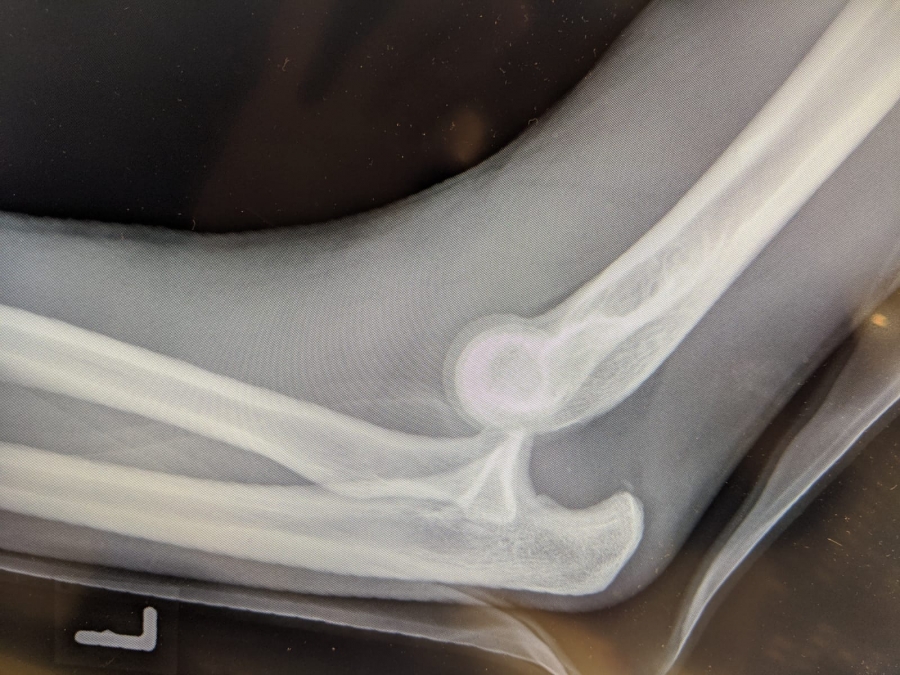

Wendrichs Röntgenbild.

Es war der 30. Dezember des vergangenen Jahres als der Sportler des LAZ Soest wie so oft auf der Hochsprungmatte in der Dortmunder Helmut-Körnig-Halle seine Turneinheit absolvierte. „Ich habe mich in der Luft etwas zu schnell gedreht, bin dann in Rücklage gelandet, von der Matte gefallen und habe mich schließlich auf dem Arm abgestützt“, erinnert sich der 24-Jährige heute. „Als der Schmerz nicht aufhörte wusste ich: Das ist etwas Schlimmeres.“ Wenig später im Krankenhaus kam dann die Diagnose: „Luxation im linken Ellenbogengelenk“. Sprich: Das Gelenk ist nicht mehr dort, wo es hingehört, es ist ausgerenkt. „Das ist eine richtig schwere Verletzung“, erfuhr Wendrich spätestens nach dem Blick auf die Röntgenbilder. Auch das Radiusköpfchen, ein Knochen am oberen Ende der Speiche, brach bei dem Sturz. Als Wendrich das Krankenhaus verließ, waren Ober- und Unterarm im 90-Grad-Winkel eingegipst und es war klar: Die Hallensaison ist gelaufen.